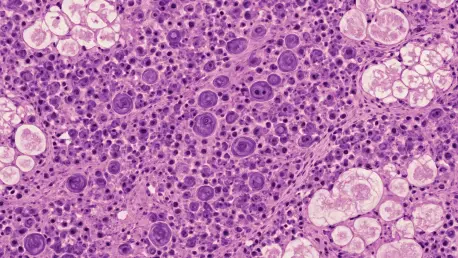

One of the most consistent recommendations from pathologists and oncologists is the indispensable role of biopsy in confirming a diagnosis of pancreatic Hodgkin lymphoma. Unlike adenocarcinomas, lymphomas rarely cause tissue necrosis or duct obstruction, a subtlety that imaging alone cannot reliably detect. Experts widely agree that invasive diagnostics are non-negotiable in cases where imaging is inconclusive or suggests a common malignancy.

Some specialists emphasize the importance of specific staining techniques during biopsy analysis to identify subtypes like nodular sclerosis, which can significantly alter treatment plans. A practical tip often shared is to ensure close collaboration with pathology teams to expedite results, minimizing delays in initiating appropriate therapies. This approach is seen as a cornerstone of tackling rare cancers effectively.